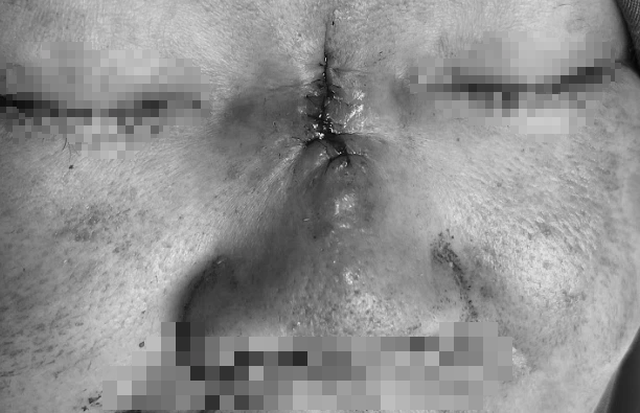

Mũi hoại tử, sưng tấy sau nâng mũi đổi vận

ẢNH: T.D

Ngày 15.10, tiến sĩ - bác sĩ Nguyễn Phan Tú Dung, Giám đốc chuyên môn Bệnh viện JW Hàn Quốc cho biết, vùng da dọc sống mũi viêm đỏ lan tỏa, phù nề và xuất hiện ổ hoại tử trung tâm màu đen, kèm thâm nhiễm mô xung quanh. Đây là dấu hiệu điển hình của thiếu máu cục bộ mô mũi do tắc mạch hoặc nhiễm trùng hoại tử mô mềm. Biến chứng này là hậu quả của việc luồn chỉ không rõ nguồn gốc, cộng với việc bơm chất lạ trôi nổi.